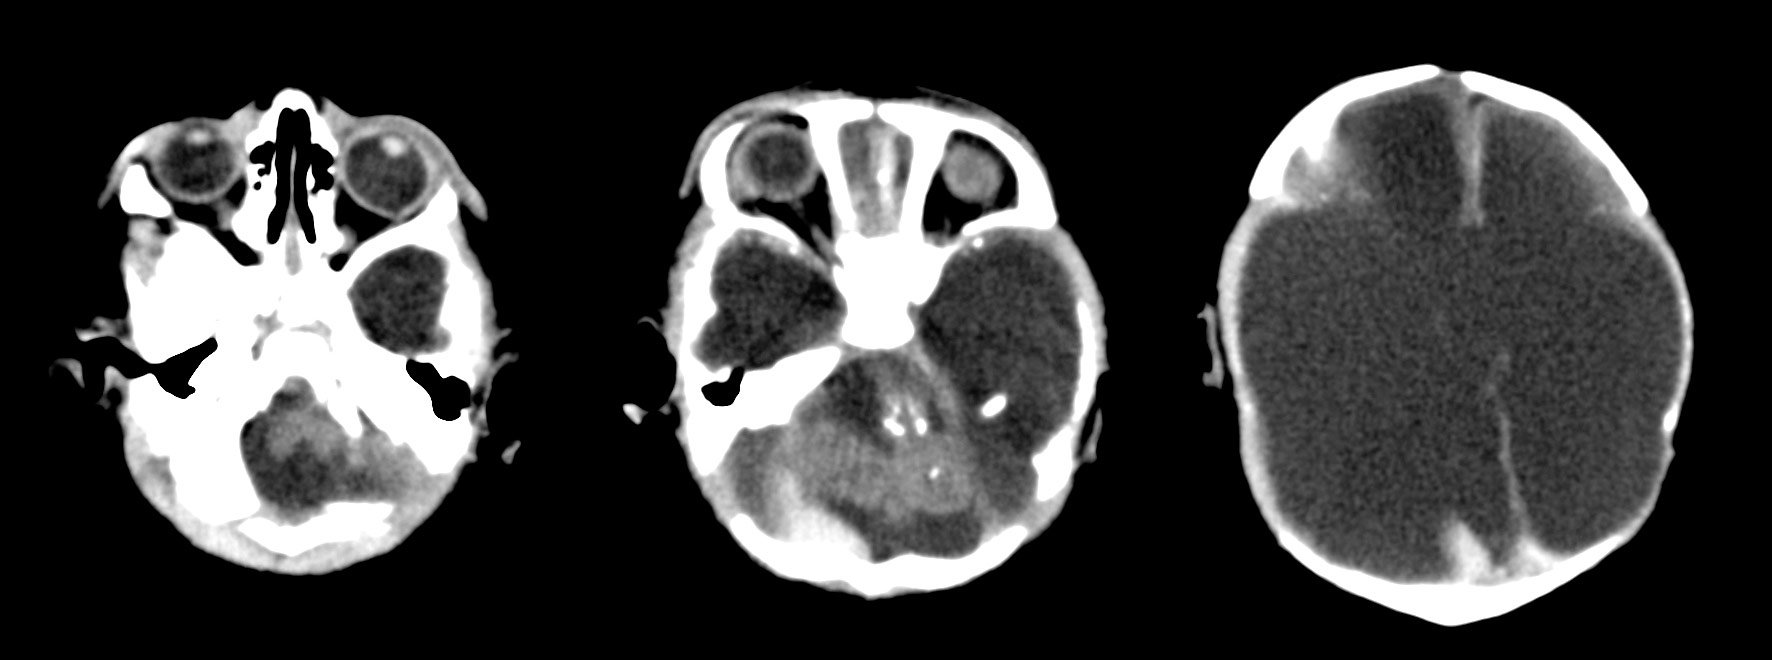

A study of brain scans and ultrasound pictures of 45 Brazilian babies whose mothers were infected with Zika in pregnancy shows that the virus can inflict serious damage to many different parts of the foetal brain beyond microcephaly, the condition of unusually small heads that has become the sinister signature of Zika.

The images, published Tuesday in the journal Radiology, also suggest a grim possibility: Because some of the damage was seen in brain areas that continue to develop after birth, it may be that babies born without obvious impairment will experience problems as they grow.

Most of the babies in the study were born with microcephaly, although three were not. Each also suffered other impairments, almost all of which emerge earlier than microcephaly because a smaller head is really a consequence of a brain that has failed to develop fully or has been damaged along the way, experts said.

“The brain that should be there is not there,” said Dr. Deborah Levine, an author of the study and a professor of radiology at Harvard Medical School. “The abnormalities that we see in the brain suggest a very early disruption of the brain development process.”